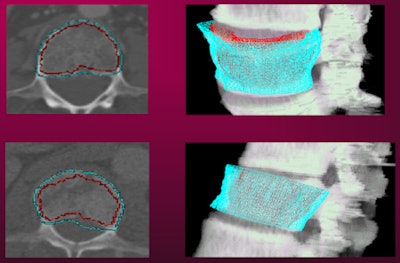

After spine segmentation and partitioning is performed, the CAD software segments the vertebral body cortical shell using a deformable dual-surfaces model that takes into account the exterior (periosteal) and interior (endosteal) surface. Next, the cortical shell is "unwrapped" by mapping the 3D cortical shell onto a 2D rectangular space, Summers said.

![]() |

| Cortical shell of the vertebral body shown on 2D (left) and 3D views (right). All images courtesy of NIH. |